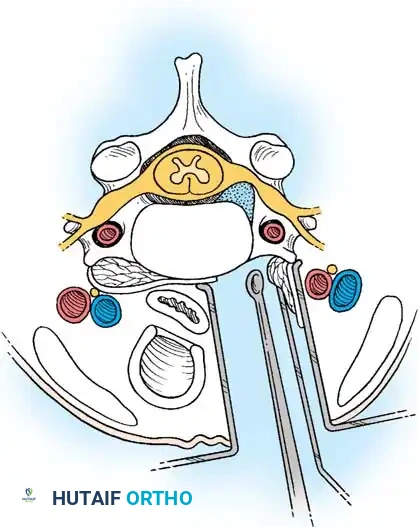

Step 2: Annulotomy and Discectomy

Self-retaining retractors are placed beneath the elevated medial borders of the longus colli. A rectangular annulotomy is performed using a #11 blade. The disc material is systematically removed using pituitary rongeurs and curettes.

Step 3: Decompression

The posterior longitudinal ligament (PLL) is carefully identified and often resected to ensure no extruded disc fragments remain in the epidural space. High-speed burrs and Kerrison rongeurs are utilized to resect posterior osteophytes and decompress the uncinate processes bilaterally, ensuring the exiting nerve roots are entirely free.

Step 4: Endplate Preparation and Fusion

The cartilaginous endplates are meticulously decorticated using a curette or burr to expose bleeding subchondral bone, which is critical for arthrodesis. Care must be taken not to breach the structural integrity of the endplate to prevent graft subsidence.

An appropriately sized structural allograft, autograft, or synthetic cage packed with osteoinductive material is impacted into the disc space under gentle cervical traction. An anterior cervical plate is then secured with screws into the adjacent vertebral bodies to provide immediate biomechanical stability.